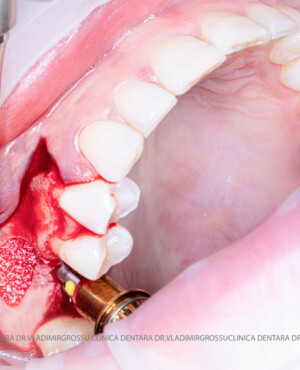

După extracția dentară, în intervalul de 6-12 luni, osul alveolar suferă un proces natural de remodelare, ceea ce conduce la scăderea volumului osos prin rezorbție. De aceea, inserția implantului dentar este ideală imediat după extracție sau, cel târziu, în primele 3-4 luni după aceasta.Scopul procedurilor de adiție osoasă este refacerea fundației osoase necesare pentru stabilizarea corectă a implantului dentar. Pentru ca un implant să reziste în timp la forțele masticatorii, este nevoie de o bază osoasă solidă și sănătoasă.

Un element esențial în procedura de aditie osoasă este utilizarea membranelor biologice, care izolează materialul osos de țesuturile moi (gingie) pe durata procesului de vindecare. Cele mai recomandate sunt membranele resorbabile din colagen sau pericard.

Aditia gingivală este o procedură chirurgicală ce corectează diverse probleme estetice și funcționale, cum ar fi recesiunea gingivală. În implantologia modernă, aditia de țesut moale este utilizată aproape în fiecare intervenție de inserție a implantului dentar pentru a asigura un aspect estetic natural și o bună integrare a implantului în cavitatea bucală.